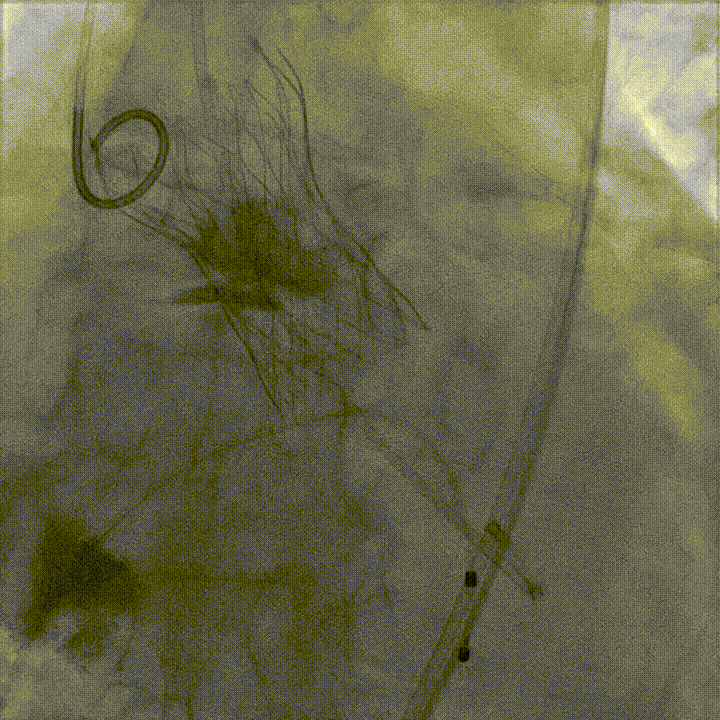

首次释放瓣膜尝试零位释放,当瓣膜释放到一半时行主动脉根部造影,发现瓣膜释放位置偏低,遂回收瓣膜重新定位后再次释放,当瓣膜释放一半时再行主动脉根部造影,发现瓣膜位置良好,遂完全释放瓣膜。

完全释放瓣膜后,经胸超声心动图显示存在轻微反流;术后造影复查显示瓣膜释放良好,轻微反流,患者情况明显改善。最后撤出导管导丝,边撤边造影,确认没有入路相关并发症,圆满完成手术。